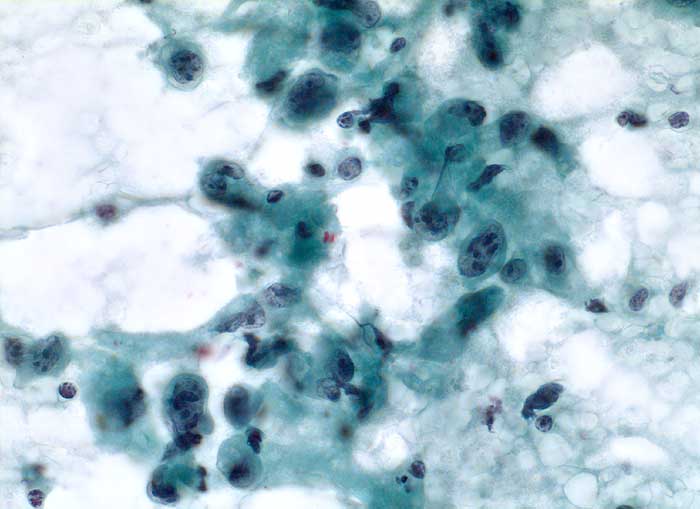

Abstriche von anaplastischen Karzinomen sind gewöhnlich sehr zellreich ausser bei ausgeprägter Desmoplasie. Die Grösse und die Form der Tumorzellen ist äusserst variabel. Oft finden sich sehr grosse, bizarre und spindelförmige Zellen. Die Kerne weisen offensichtliche Zeichen der Malignität auf: irreguläre Kernmembran, grobes dunkles Chromatin und Makronukleolen. Mitosen, auch atypische, sind häufig. Das Zytoplasma variiert von blass und vakuolisiert über granulär bis dicht. Nekrosen, neutrophile Granulozyten und eine Tumordiathese im Hintergrund sind typisch. Die Tumoren exprimieren Vimentin und Zytokeratine, sind aber negativ für Thyreoglobulin und TTF1 (Thyroid Transcription Factor).